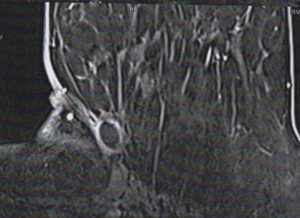

Une lésion suspecte au niveau du sein gauche

Mme S, 82 ans, nous consulte car elle a noté un nodule au niveau de son sein gauche (Fig. 1). Cette patiente est hypertendue, insuffisante cardiaque, mais est actuellement bien équilibrée…